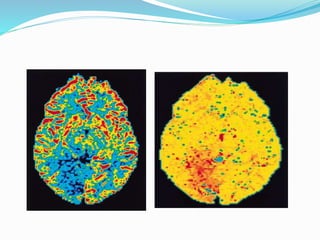

 MR Perfusion in Stroke

 Mismatch between PW and DW represent potentially

salvageable tissue (penumbra). PW-DW mismatch is

also indicator of clinical outcome. Small mismatch has

good clinical outcome. Large mismatch is associated

with poor clinical outcome and larger vessel occlusion.